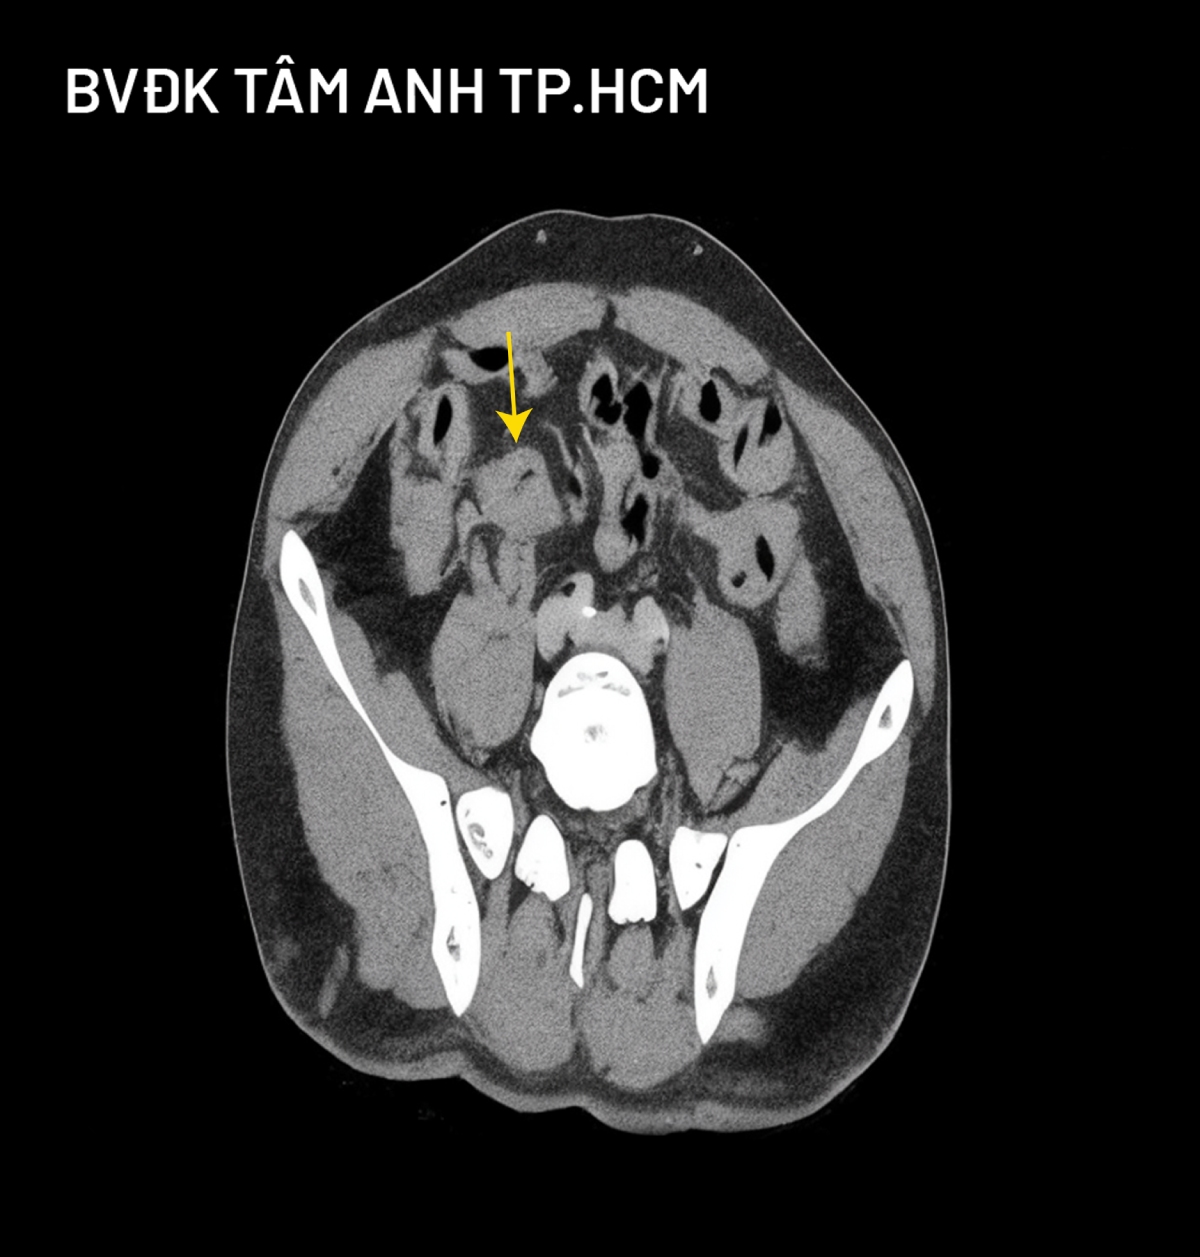

Kết quả nội soi đại trực tràng phát hiện một số polyp, khối u sùi lớn ở manh tràng – đại tràng lên gây biến dạng và hẹp van hồi – manh tràng khiến ống soi không thể đi qua. Kết quả giải phẫu bệnh là ung thư biểu mô tuyến xâm nhập, biệt hóa vừa. Hình ảnh sinh thiết tổn thương gan qua nội soi siêu âm cũng cho thấy ung thư đại tràng di căn gan.

Tiến sĩ, bác sĩ Phạm Công Khánh, Trưởng khoa Gan – Mật – Tụy, Trung tâm Nội soi và Phẫu thuật Nội soi Tiêu hóa, cho biết người bệnh được chẩn đoán ung thư manh tràng – đại tràng lên giai đoạn muộn, đã di căn gan tại hạ phân thùy III.

Quá trình mổ, bác sĩ ghi nhận bụng trướng nhiều, các quai ruột non giãn lớn, không có không gian để mổ nội soi nên chuyển sang mổ mở. Khối u manh tràng – đại tràng lên xâm lấn thanh mạc, gây tắc hoàn toàn van hồi – manh tràng, kèm nhiều hạch vùng. Bác sĩ tiến hành di động đại tràng phải, cắt ngang hồi tràng cách góc van hồi manh tràng 20 cm và đại tràng ngang cách góc gan 5 cm, nối hồi tràng – đại tràng ngang bằng máy khâu nối. Khối u gan di căn phân thùy III kích thước 4 cm, sát bề mặt dưới gan; di động thùy trái gan, cắt nhu mô gan, kẹp và cắt cuống gan hạ phân thùy II-III và tĩnh mạch gan trái.